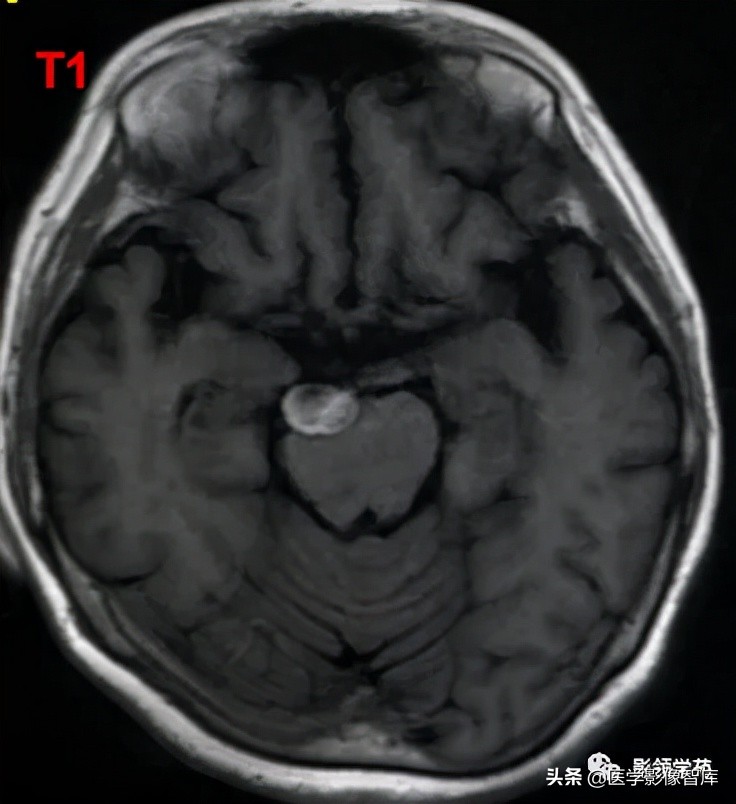

女 58岁,头晕、呕吐,桥脑右前方见一类圆形

高低混合(有血栓)T1及T2信号影,边界清楚、锐利。

明显不均匀强化(瘤内有血栓)。与基底动脉分界不清

头颅CTA:基底动脉起始部血管局部瘤样突起(宽基底),无占位效应。